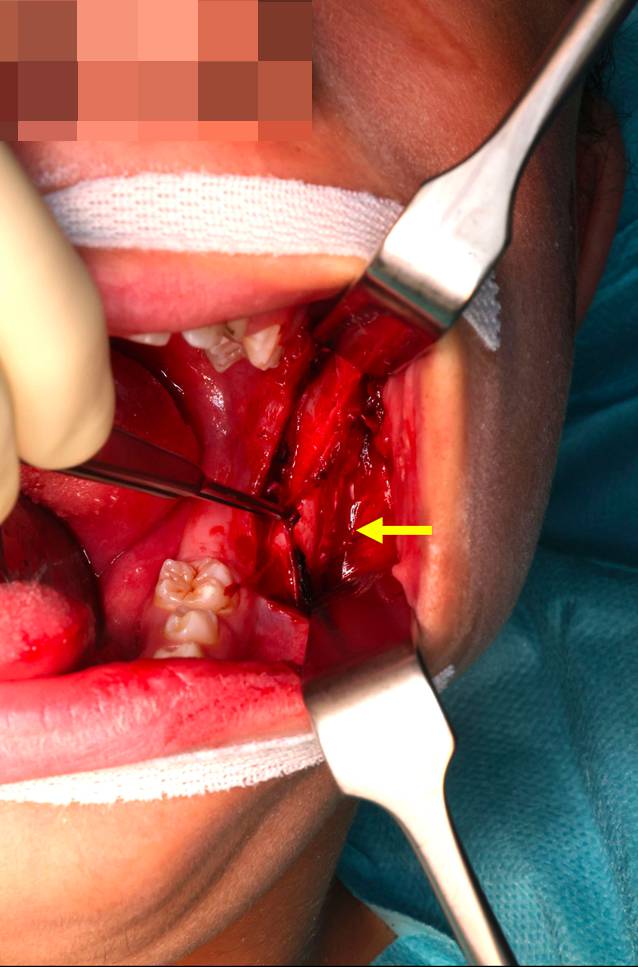

Abb. 4

Operationssitus: supraperiostale Präparation der intramuskulären Raumforderung (Pfeil)